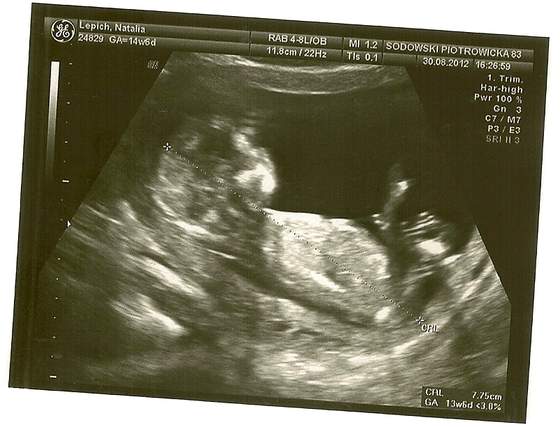

Zdjęcia z USG, wizyty lekarskie, badania...

Wszystko z dzidziusiem OK. Ma wszystko co powinien mieć, przezierność niska (1,7), kość nosowa jest;) Są dwie ręce, dwie nogi, dwie półkule w mózgu ;) wszystko ma tam gdzie powinien;) No i Pan doktor powiedział, że o flaszkę wódki się założy, że to CHŁOPCZYK ;)

Od razu wrzucam zdjecia :)